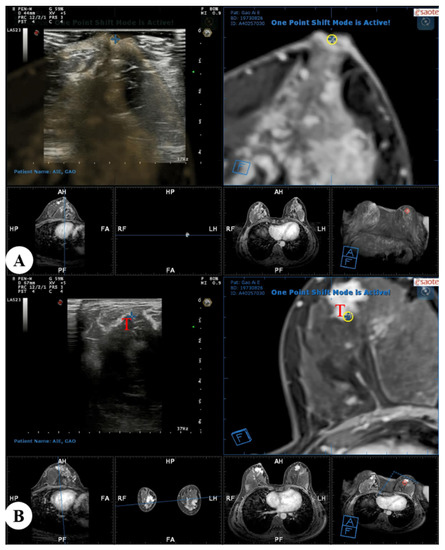

Figure 3.

Real-time US with virtual navigation was performed in the prone position: (A) A co-registration process between real-time US and MRI-MPR images was performed with the nipple as a reference point, and the contour of the breast and internal anatomic landmarks were aligned; (B) Search and localization using real-time US with virtual navigation of the corresponding suspected enhanced lesion (T, target) identified on MRI alone. US = ultrasound; MRI = magnetic resonance imaging; MPR = multiplanar reconstruction.